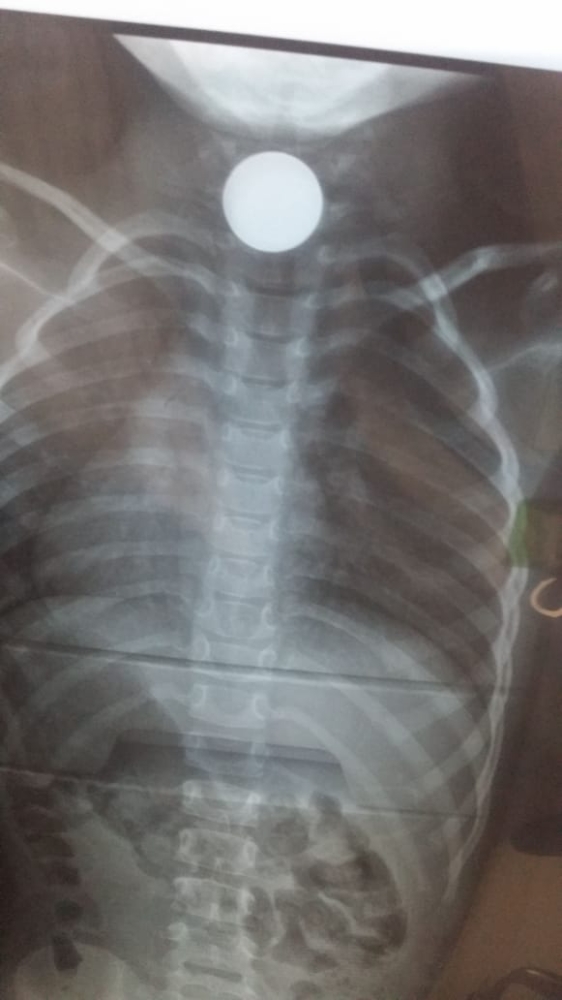

نجح فريق طبي بمستشفى الملك فهد بجازان، في استخراج قطعة معدنية علقت بحنجرة طفلة.

وكان قسم الطوارئ بالمستشفى استقبل الطفلة صبا عبدالرحمن، وهي تعاني من قيء وسعال وضيق في عملية البلع، وبعد التشخيص اتضح في الأشعة وجود جسم غريب بالمريء، وتم نقلها إلى قسم العمليات تحت التخدير العام وخضوعها لعملية جراحية، واستخراج قطعة نقدية عن طريق المنظار. وغادرت الطفلة المستشفى وهي بصحة جيدة.

استخراج قطعة نقود من حنجرة طفلة